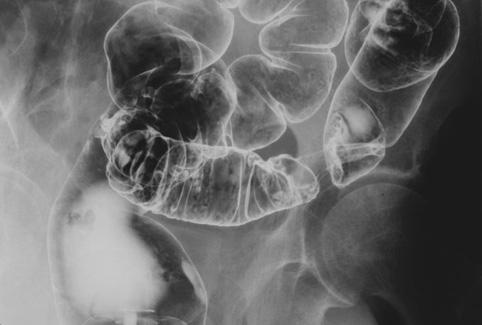

Criteria of Hist.ClassificationMalignant epithelial tumor/Adenocarcinoma

LocationLarge intestine(Colon)/Sigmoid colon

Technique, MethodX-ray

Macroscopic TypesType 1 Protuberant (polypoed) type/

Size30 - 34

Depth of Tumor Invasionserosa (adventitia)